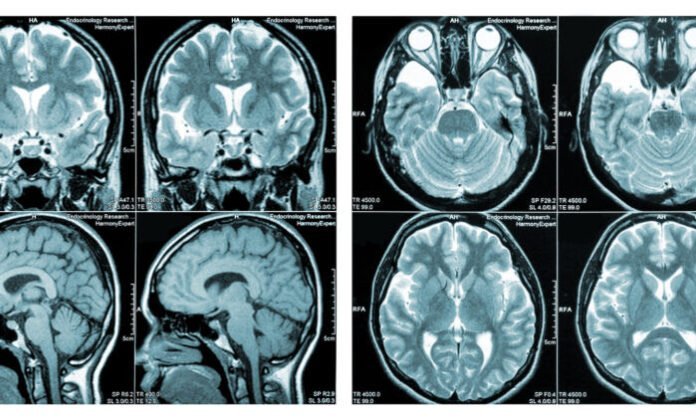

Brain injuries refer to any damage that occurs to the brain due to external or internal factors. These injuries can vary in severity and lead to a range of symptoms, including headaches, dizziness, loss of consciousness, and even permanent disability.

Types of brain injuries

Brain injuries can be classified into several types based on the severity and location of the injury. One of the most common types is a concussion, which occurs due to a blow to the head or sudden jolt that causes the brain to move rapidly within the skull. Concussions usually result in temporary loss of consciousness or confusion.

Another type of brain injury is a contusion, which is characterized by bruising or bleeding in one specific area of the brain. This type of injury typically occurs when there is direct impact to the head, such as with a car accident or fall.

A diffuse axonal injury (DAI) happens when there is rotational force involved, causing widespread damage throughout multiple areas of the brain. This can occur during high-speed accidents like car crashes and falls from great heights.

Cerebral edema refers to swelling in the brain caused by fluid buildup after an injury. This can put pressure on different parts of your brain and lead to additional complications such as seizures and coma.

Penetrating injuries happen when an object penetrates through your skull and enters your brain tissue directly. These are often serious injuries that require immediate medical attention.